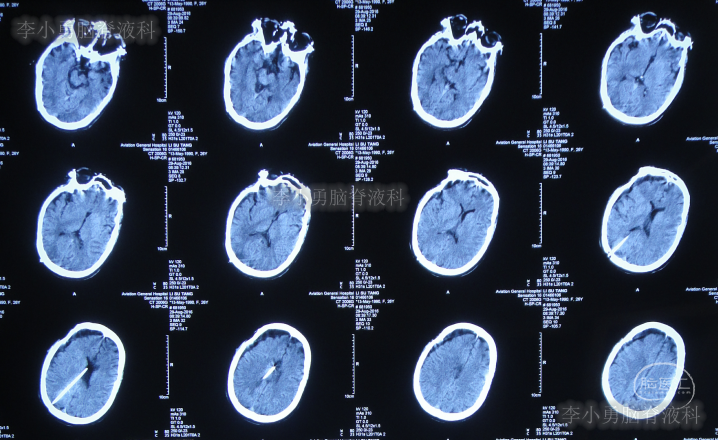

第三家医院第3次门诊图-1

图-1:2016年3月18日头颅CT